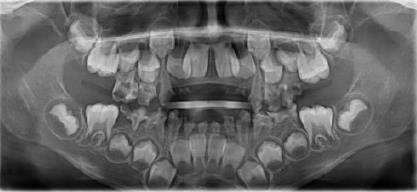

上麵那張牙齒嚴(yan) 重齲壞的牙齒的片子

但如果蛀牙已經感染到根尖炎(一般需要拍片才能看出),那麽(me) 蛀牙細菌流可能會(hui) 禍害下麵的恒牙胚,從(cong) 而影響恒牙長出來。比如,常見的可能會(hui) 造成萌出的恒牙牙釉質發育不良,牙齒顏色異常、容易蛀牙等。